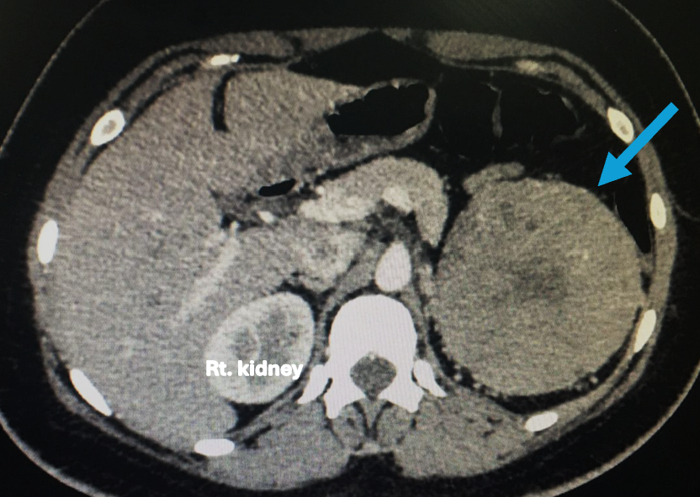

A CT scan revealed a large, mildly enhancing mass in the upper pole of the left kidney, measuring 93 x 92 x 96 mm (Figure 1).